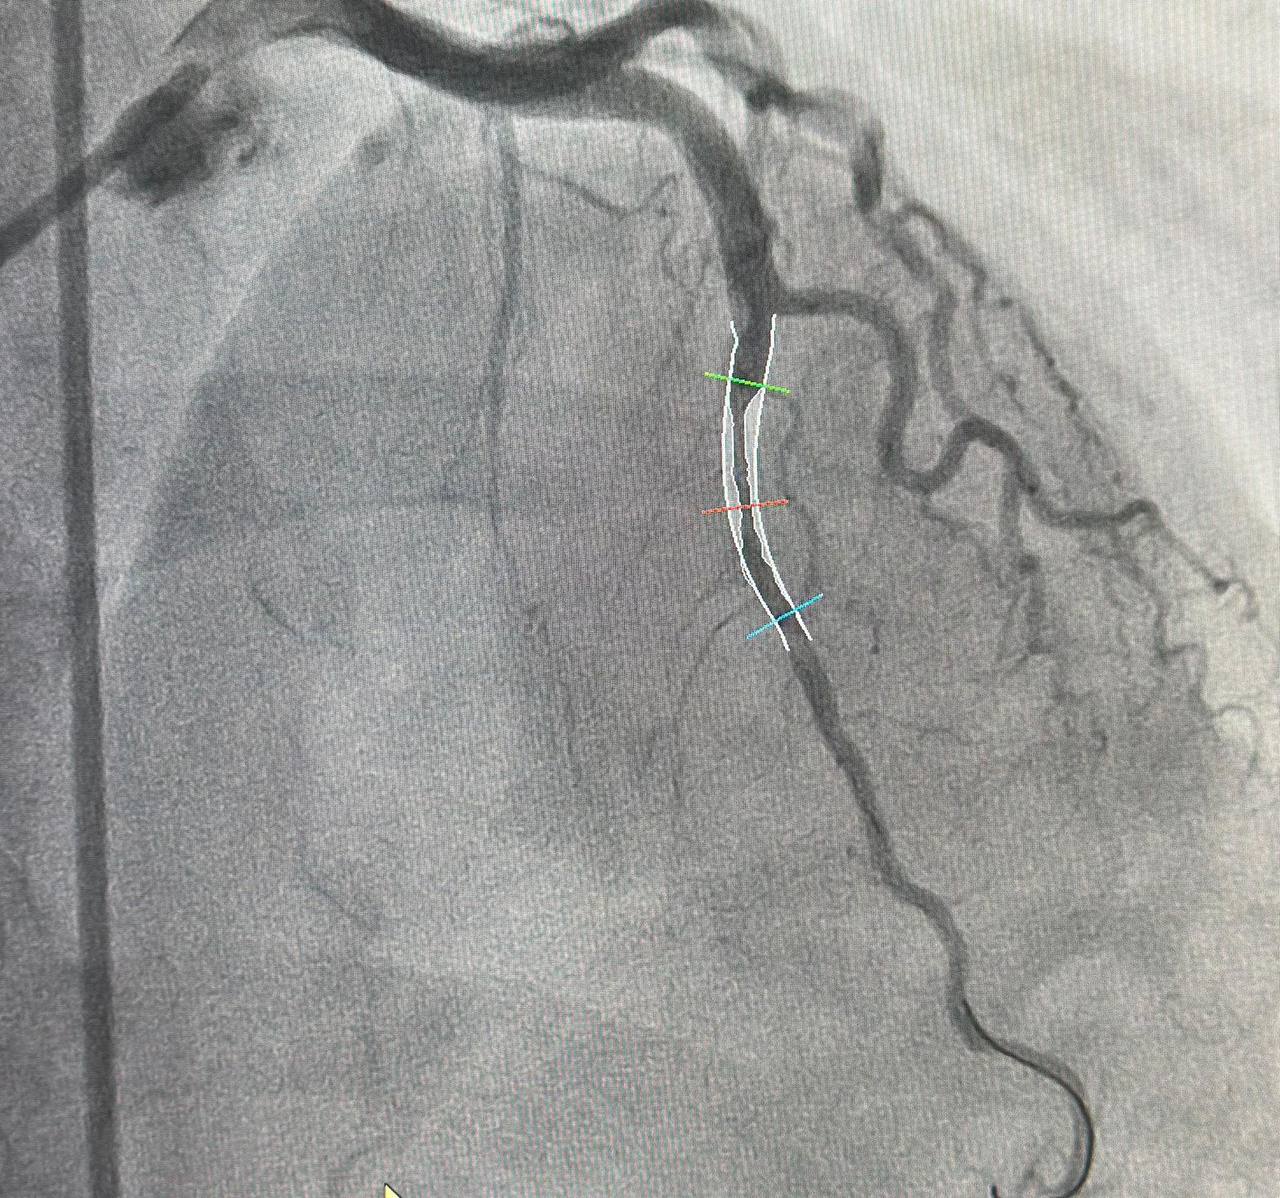

Врачи выполнили стентирование, чтобы артерия снова стала проходимой, а лекарствами восстановили нормальный ритм сердца. При выписке пациентка сказала: «Как заново родилась!»